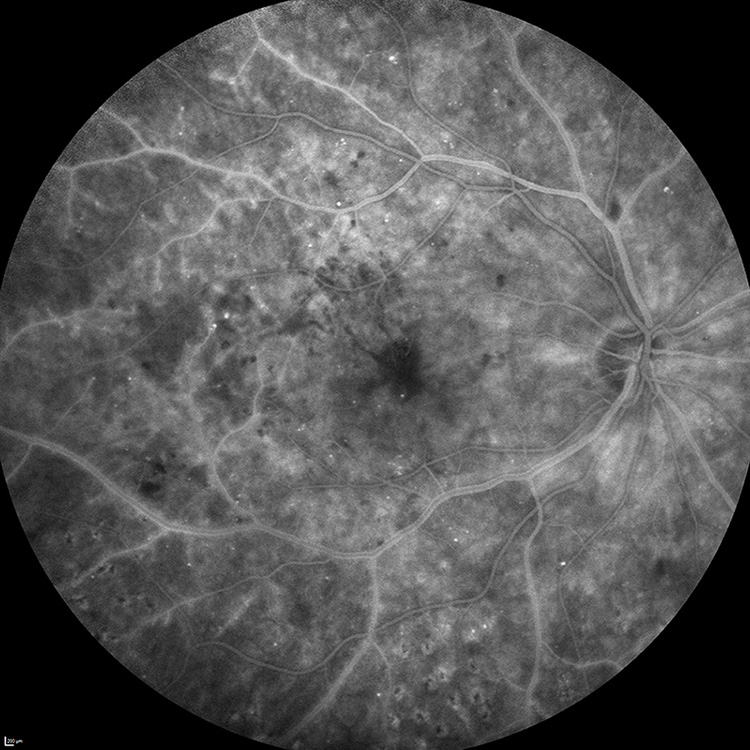

Angiographie à la fluorescéine

Enfin, une angiographie à la fluorescéine offre une vue d’ensemble de toutes les lésions vasculaires liées à la rétinopathie diabétique. Elle permet notamment de détecter les zones d’ischémie rétinienne pas toujours visibles au fond d’œil et de vérifier la perméabilité des capillaires de la rétine, particulièrement utile pour guider le choix du traitement thérapeutique.